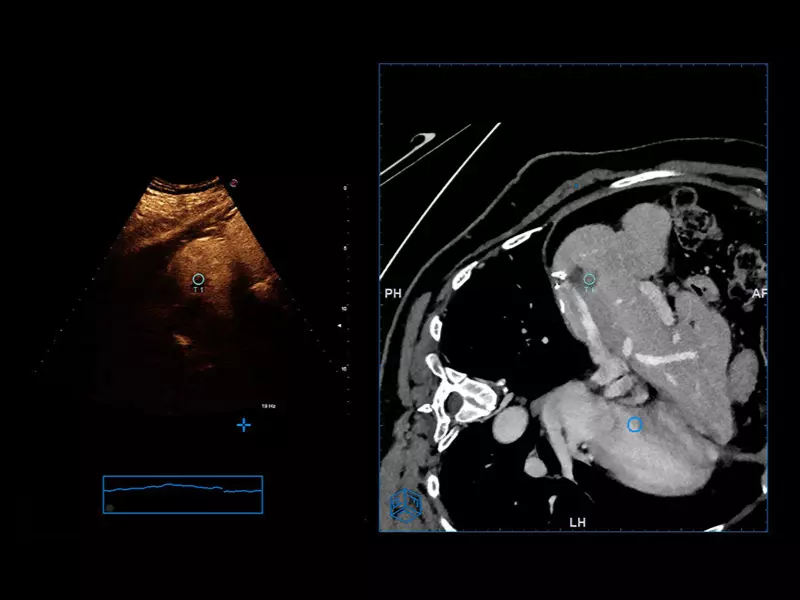

MyLab™E80 - VNav - Liver Fusion

MyLab™E80 - VNav - Liver Fusion